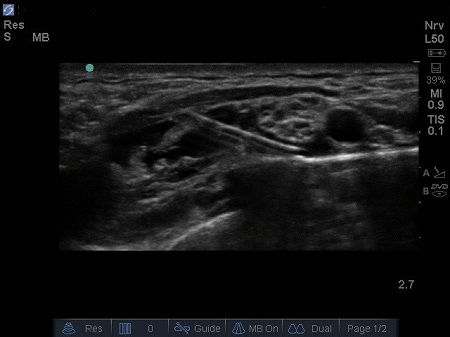

- The first structure to locate is the round pulsating hypoechoic subclavian artery (A), lying on top of the hyperechoic first rib (R). Use Doppler to assess for vessels. See Fig. 2.

Fig. 2. Bidirectional Doppler used here to highlight the subclavian artery.

- The subclavian vein (V) is found more medially to the artery. The anterior scalene muscle inserts onto the first rib between these two vessels (A and V), but occasionally there are anatomical variations (4) where both vessels are together between the insertions of both the scalene muscles (anterior and middle ones).

- A linear hyperechoic structure immediately deep and lateral to the A is the first rib with its bony shadow. However, in small children the cortical layer of ribs is thin enough that you can see both layers of the rib cortex and visualise lower down another bright line: the parietal and visceral pleura interface. See Fig. 3.

- Lateral and above the artery sit a bundle of round hypoechoic circles (“bunch of grapes” or “cluster of bubbles”) – the brachial plexus, at this level, the plexus will be configured as trunks and/or divisions.

- It may be possible to identify the hypoechoic nodules surrounded by a hyper-reflective fascial sheath.